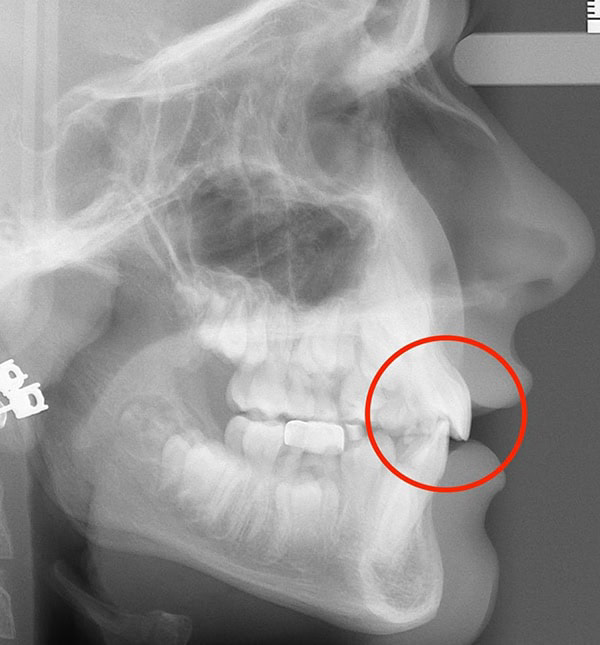

Actual Patient: Alexander

After

After

Severe “Underbite”, Narrow Jaws, Adult Teeth Not Growing In

Front View

Top View

Right & Left Sides